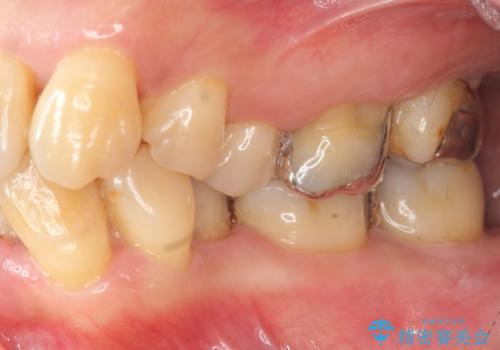

- 重度の歯周病に罹患しており、他院で「多数の歯を抜歯したのち、入れ歯を入れるしかない。」と言われ、入れ歯以外の方法がないか相談のため来院されました。

重度の歯周病で多数の歯を残せない問題、歯並び・噛み合わせの問題、欠損の問題、と多数の大きな問題が認められました。

このままの歯並びでは仮にインプラントを埋入したとしても歯ブラシがしづらく、また歯周病の問題が再発しやすい、と判断し矯正治療を行ったのちに歯周病治療、インプラント治療を行っていく治療計画としました。